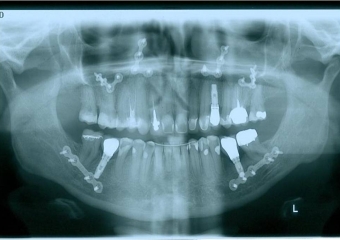

Raio x panorâmico final